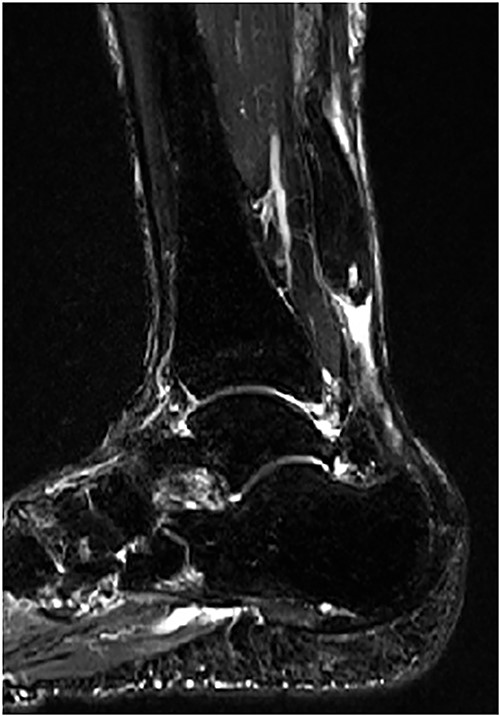

The operation (Fig. 4) and postoperative treatment performed were the same as Case 1.

(A) In the rupture site, scar tissues and degenerative tendon were confirmed. (B) The operation was performed as same as Case 1.